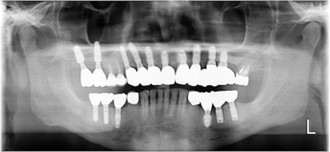

50代 男性

治療前

治療後

治療後- 年齢/性別

- 50代/男性

- 主訴

- 上顎の義歯の具合が悪いため、インプラント希望

- 治療期間

- 1年間

- 治療費

- インプラント¥4,400,000

骨造成¥220,000

サージカルステント¥99,000 - リスク・副作用

- 術後の腫れ・出血